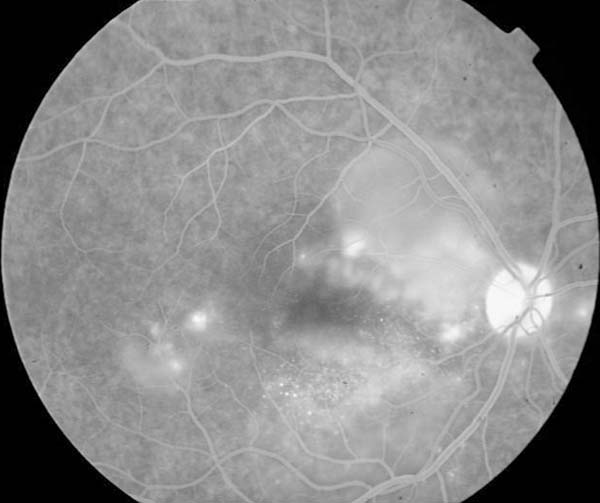

Se deriva a la paciente para valoración neurológica urgente, y se programa para estudio angiográfico. Cuatro días después vuelve a consultar con urgencia por pérdida de visión bilateral. En esos momentos la agudeza visual era de visión de bultos en ambos ojos y la imagen funduscópica sugestiva de neurorretinitis bilateral (fig. 2).

La angiografía fluoresceínica revelaba en ambos ojos varios puntos de filtración en tiempos precoces con importante difusión en los tardíos (figs. 4 y 5).

Fig. 4: AGF. Tiempos precoces.